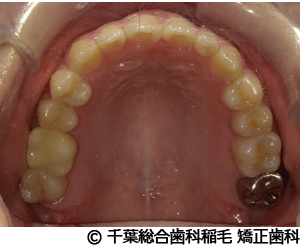

【症例2】マウスピース型矯正装置「インビザライン」

- 治療前

- 治療後

- 治療名

- マウスピース型矯正装置「インビザライン」

- 費用

- 700,000円(税込)

- 期間

- 1年

すきっ歯(空隙歯列)。

上顎前歯の隙間が気になると、当院にご相談に来られました。 -

抜歯はなし。

全顎をマウスピース型矯正装置「インビザライン」を用いて矯正治療を行いました。 -

空隙歯列の上顎前歯が改善され、さらに下顎の歯列も矯正したため、審美面・機能面の回復に繋がりました。

※治療結果は患者様によって個人差があります。

治療を行う上での注意点(リスク・副作用)

むし歯、痛み、歯根吸収、後戻り、口内炎、発音障害